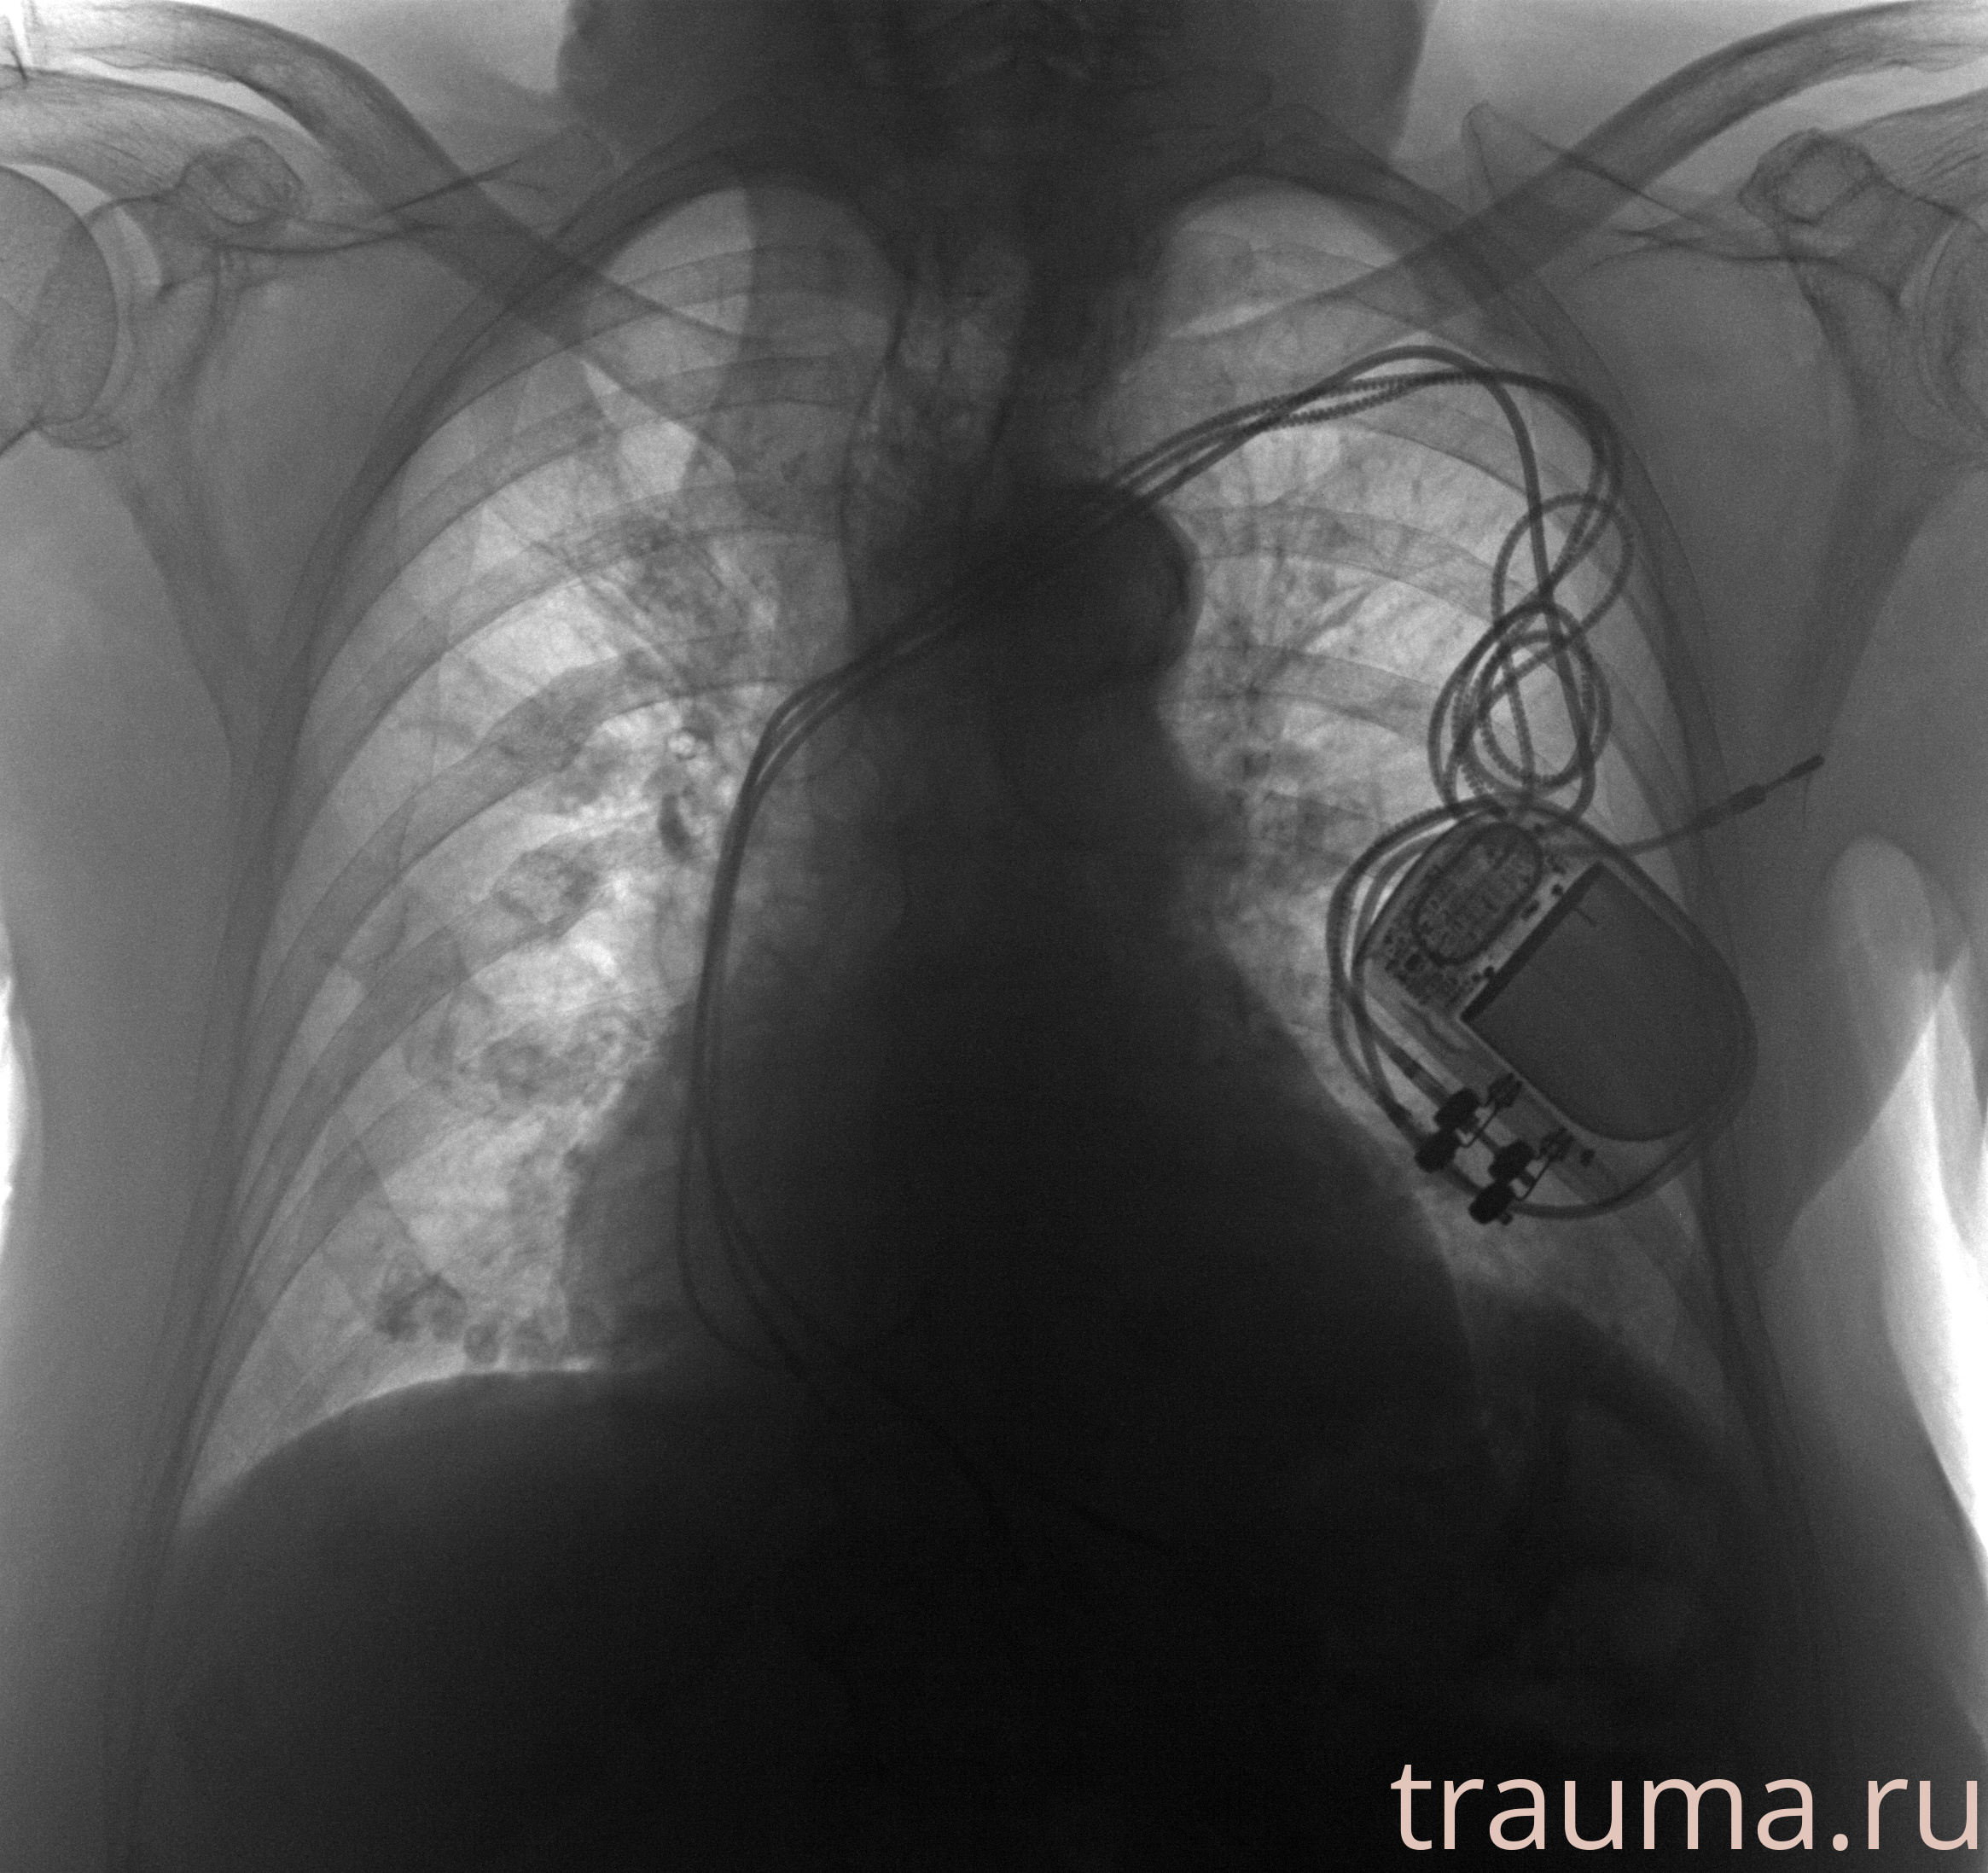

Рентгенограммы

Рентген на дому: по вашему адресу приезжает врач-рентгенолог, травматолог-ортопед с мобильным рентгеновским аппаратом, проводит диагностику травмы или заболевания, делает необходимые рентгенограммы, дает рекомендации по дальнейшему лечению. Получить качественные снимки в домашних условиях возможно благодаря уникальной методике, разработанной МосРентген Центром для института  Склифосовского

при переломе шейки бедра и пневмонии от компании МосРентген Центр - партнера Института имени Склифосовского